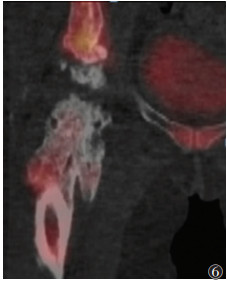

晚期病变21例,X线(21例)、CT(15例)、MRI(11例)及SPECT/CT(15例)阳性率均为100.0%。X线或CT表现为软组织内团状密度增高影,边界清晰,其中9例与相邻骨骼相连,与皮质分界不清,但髓腔不受累。MRI表现为肿块内广泛的T1WI高信号、T2WI低信号(骨化),9例病灶内含T1WI等信号、T2WI高信号、STIR低信号影(脂肪)(图 5)。SEPCT/CT显像15例,其中3例病灶中央及周围均未见显像剂摄取(图 6);6例病灶中央显像剂不均匀摄取(图 7);6例病灶周围显像剂不均匀摄取(图 8)。

| 图 6 女,50岁,右髋关节骨化性肌炎(晚期)。SPECT/CT冠状位融合图像,显示右侧髋关节骨化性肌炎病灶中心及周缘均未见明显显像剂摄取 |

3.3 晚期外伤后5~6个月,肿块开始收缩,周围水肿减轻乃至消失,此期影像学诊断相对容易。X线或CT表现为边界清晰的团块状骨化,可与相邻骨骼相连,与皮质分界不清,但髓腔不受累;MRI表现为肿块内广泛的双低信号,其内可含脂肪信号。但本研究中晚期患者的SPECT/CT特征不一致,可表现为病灶完全无显像剂摄取或病灶中央显像剂高摄取而周围无摄取,也可能表现为中央无显像剂摄取而周围高摄取。提示骨化性肌炎的骨化可能是一个复杂的过程,具体机制有待进一步研究。